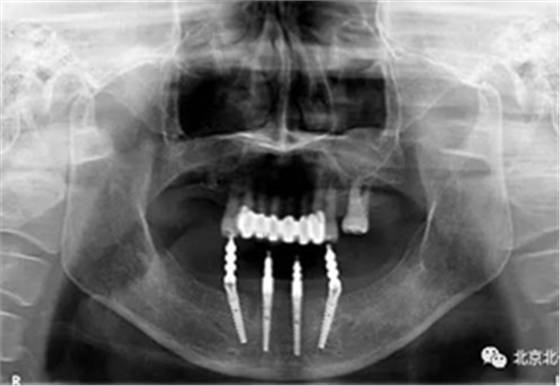

圖十五:術(shù)后即刻拍X片

圖十七:拍X片確認無誤差